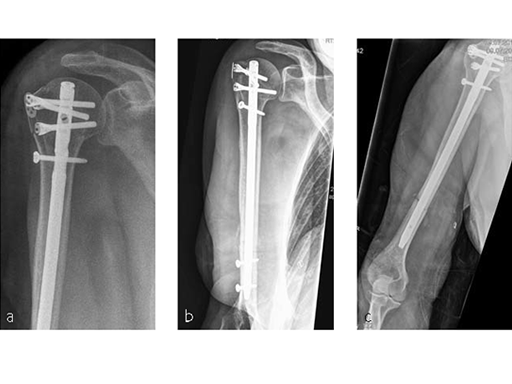

Long MultiLoc Nail

A long version of the MultiLoc nail (Fig 3) was developed in order to treat such issues as fractures of the humeral diaphysis, fractures of the proximal humerus with diaphyseal extension, as well as combined fractures of the proximal humerus and the humeral diaphysis. This longer version nail, which is available in 7.0 mm and 8.5 mm diameters and in lengths from 180 mm to 315 mm, completes the MultiLoc Humeral Nailing System creating a single comprehensive system for all fractures amenable for nailing.

Following a fall downstairs, a 70-year-old woman sustained a head injury with intracerebral and subdural haematoma, as well as a complex fracture of the right humerus, representing a minimal displaced proximal and an oblique fracture in the distal part of the humerus (Fig 11).

After neurosurgical intervention, surgery of the humerus was planned 10 days after the index trauma. The patient was still at the neurological intensive care unit and a preoperative clinical examination of the patient, regarding radial nerve palsy, was not possible. Therefore, a surgical revision with exploration of the radial nerve and an osteosythesis of the humerus using a long MultiLoc Humeral Nail was indicated.

The patient was operated on in beach chair position. For the exploration of the radial nerve, a limited anterolateral approach was used. The nerve was mobilized and retracted laterally. An anterolateral approach to the proximal humerus was performed. The supraspinatus showed a small acute rupture without retraction. The supraspinatus tendon was split to get access to the insertion area on the humeral head. A 270 mm long MultiLoc Humeral Nail of 8.5 mm diameter was inserted under visual and x-ray control to the desired endpoint. Reduction of both the proximal and the distal humerus fracture was anatomical. In the lateral view there was a small gap, and it was decided to apply compression after distal locking (Fig 12). Proximally, three MultiLoc screws were inserted and a 2 mm end cap was placed. Finally, the supraspinatus rupture was reconstructed with transosseous sutures and secured with an augmentation plate. The posterior greater tuberosity fracture was secured with Fiber Wire to the MultiLoc screws. Fig 13 illustrates the definitive fixation.